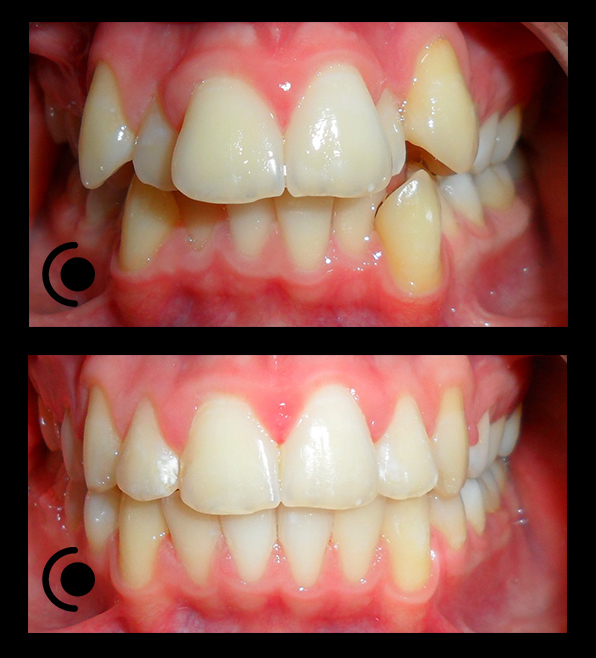

O našoj kvaliteti najbolje govore naši rezultati!

Centar za ortodonciju Petra Džapo